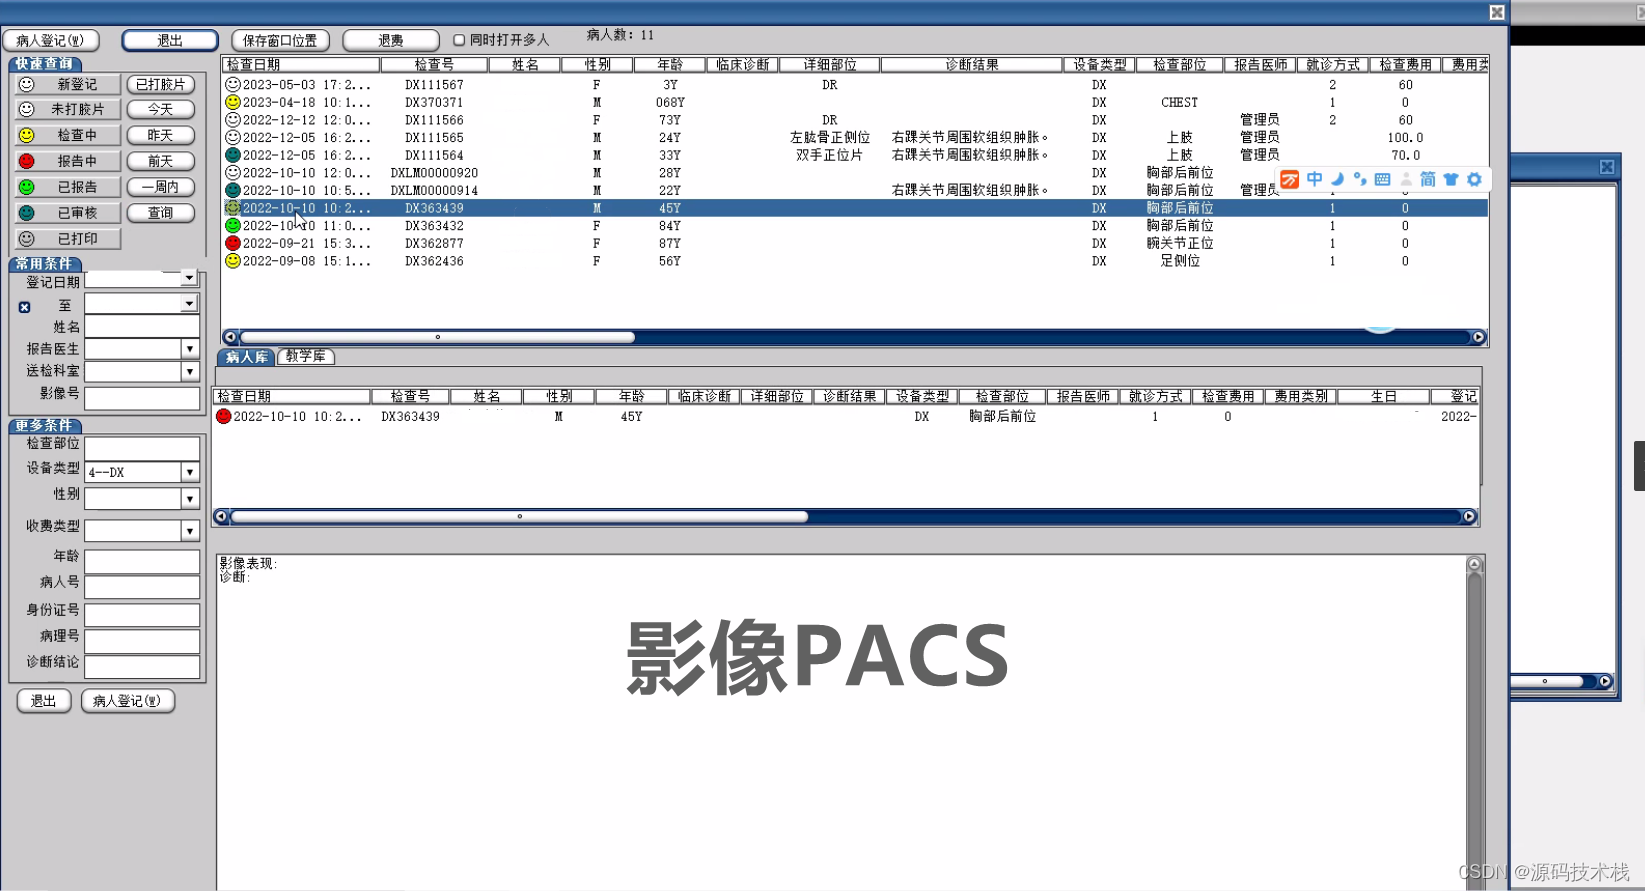

影像检索:PACS可以通过患者的个人信息(如姓名、病历号等)或影像的特征(如日期、影像类型等)进行检索,快速找到需要的影像数据。

影像传输:PACS可以通过网络将影像数据传输到医生、技师等相关人员的工作站上,实现远程查看和诊断。这样可以方便医生之间的协作和远程会诊。

RIS:为Radiography InformationSystem的缩写,是放射科信息系统。RIS主要功能和应用包括病人检查预约,影像设备管理与预定,医嘱的输入与管理,病人与设备预约的管理,影像诊断报告和生成与管理,划价,收费。

功能包括:预约分诊、排队叫号、放射/医技科室信息管理系统、影像处理、医技报告书写、WEB图像浏览(院内)、影像报告发放/共享。